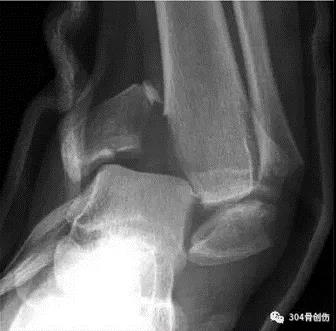

x线检查

术前DR